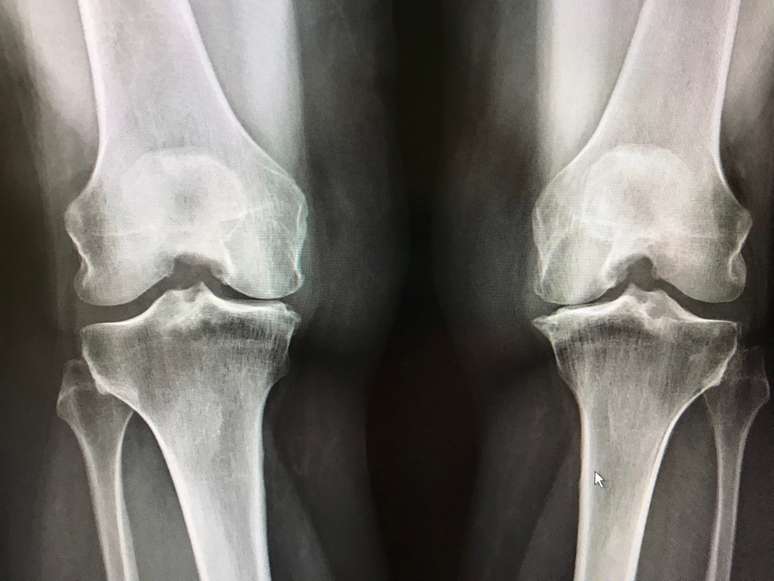

Raio-X de uma pessoa com Displasia Metafisária Tipo Schmid

Foto: Vakinha / Vakinha